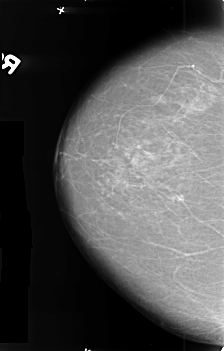

B_3412_1.RIGHT_MLO

RIGHT_CC LINES 4560 PIXELS_PER_LINE 2904 BITS_PER_PIXEL 12 RESOLUTION 50 NON_OVERLAY

RIGHT_MLO LINES 4664 PIXELS_PER_LINE 2904 BITS_PER_PIXEL 12 RESOLUTION 50 NON_OVERLAY